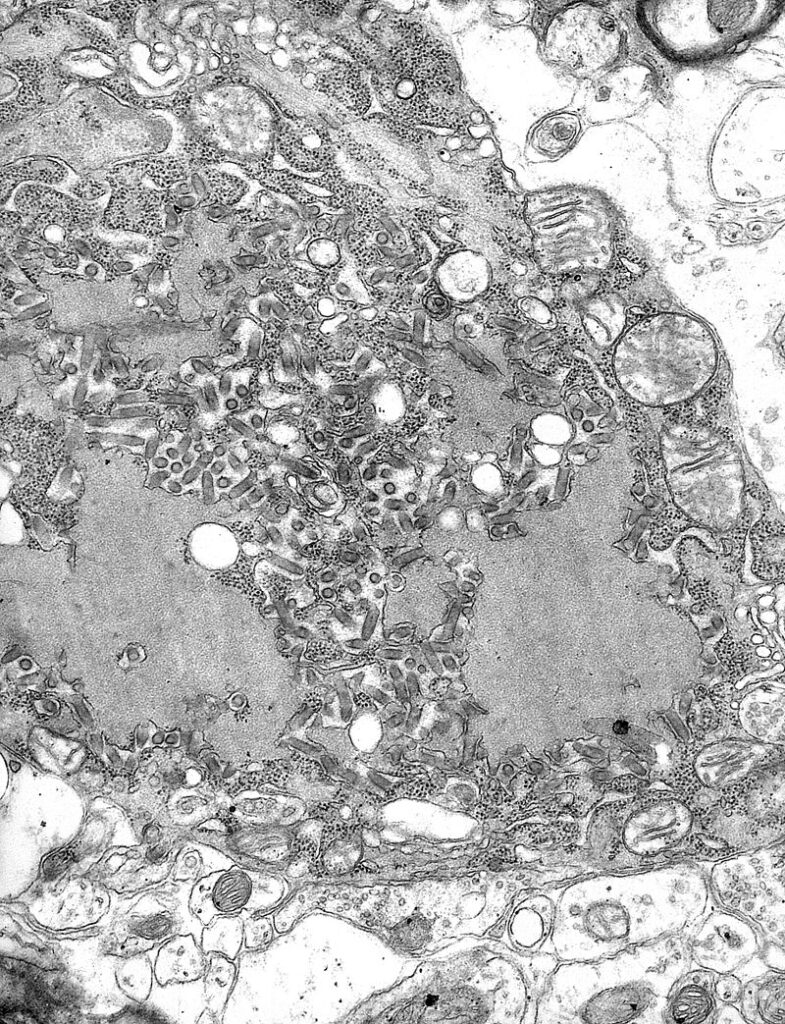

Imagen de microscopía electrónica del virus de la rabia y de los cuerpos de Negri (inclusiones celulares). CDC/Dr. Fred Murphy, 1975. Fuente: Wikimedia Commons.